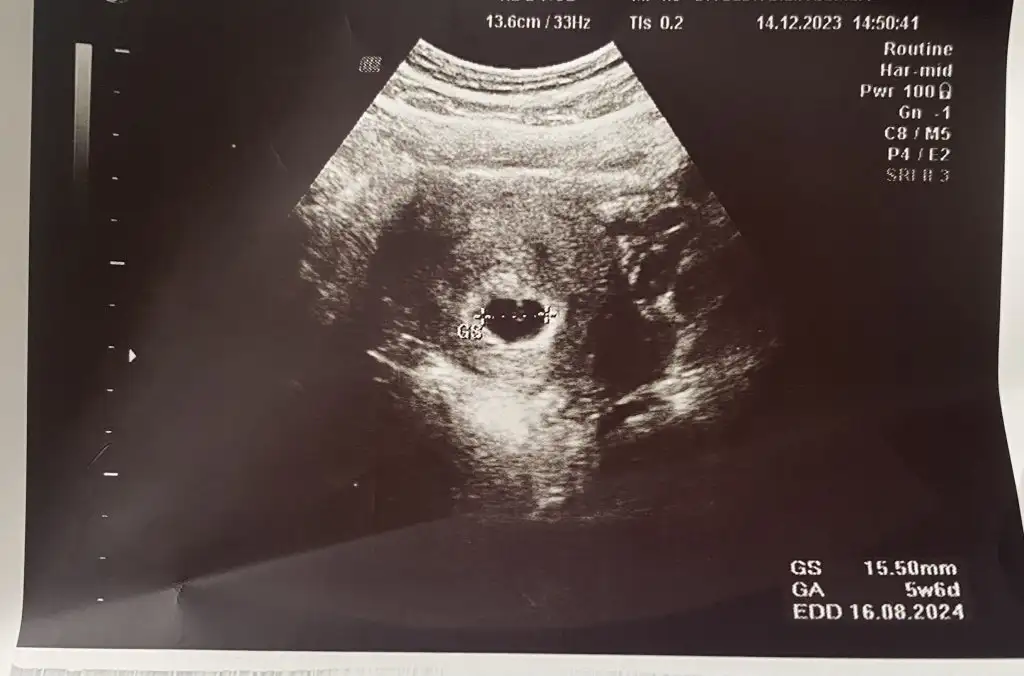

U umaycayBuraya kendi ultrason çıktımı bırakıyorum . Çıktıdan, nispeten iyi bir cihaz olduğu anlaşılıyor . Bazı çıktılar çok bulanık , ordan da cihazın eski ya da bozuk olduğu anlaşılıyor. Sen bence farklı bir doktora git . Çünkü 10 gün beklemek için çok uzun . Burda kese görünmedi , bebek görünmedi diyen yorumlar çok fazla . Çoğu da başka doktora gidip bebekleri gördüler canım . Sende git ki için rahatlasın Eki Görüntüle 3353389

Buraya kendi ultrason çıktımı bırakıyorum . Çıktıdan, nispeten iyi bir cihaz olduğu anlaşılıyor . Bazı çıktılar çok bulanık , ordan da cihazın eski ya da bozuk olduğu anlaşılıyor. Sen bence farklı bir doktora git . Çünkü 10 gün beklemek için çok uzun . Burda kese görünmedi , bebek görünmedi diyen yorumlar çok fazla . Çoğu da başka doktora gidip bebekleri gördüler canım . Sende git ki için rahatlasın

Canım cidden senin ultrasonda görüntü kalitesi çok net ben özele gitmeme rağmen bu kadar net çıkmadı açıkçası bu biraz moral bozucu pazartesi günü gideceğim inş kesenin içinde bebeği görürüz ve kalp atışını duyarızBuraya kendi ultrason çıktımı bırakıyorum . Çıktıdan, nispeten iyi bir cihaz olduğu anlaşılıyor . Bazı çıktılar çok bulanık , ordan da cihazın eski ya da bozuk olduğu anlaşılıyor. Sen bence farklı bir doktora git . Çünkü 10 gün beklemek için çok uzun . Burda kese görünmedi , bebek görünmedi diyen yorumlar çok fazla . Çoğu da başka doktora gidip bebekleri gördüler canım . Sende git ki için rahatlasın Eki Görüntüle 3353389